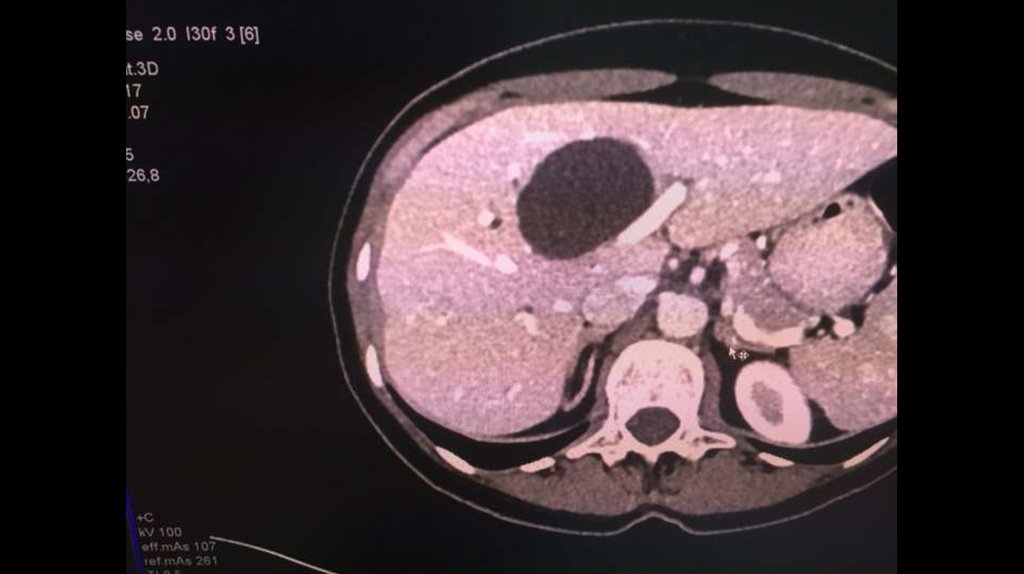

По направлению из ЦГБ в ККБ №1 поступил пациент М., 48 лет, с диагнозом «Эхинококкоз

печени»

Пациенту в плановом порядке выполнено КТ ОБП. По результатам исследования выявлена

эхинококковая киста IV-V сегментов.